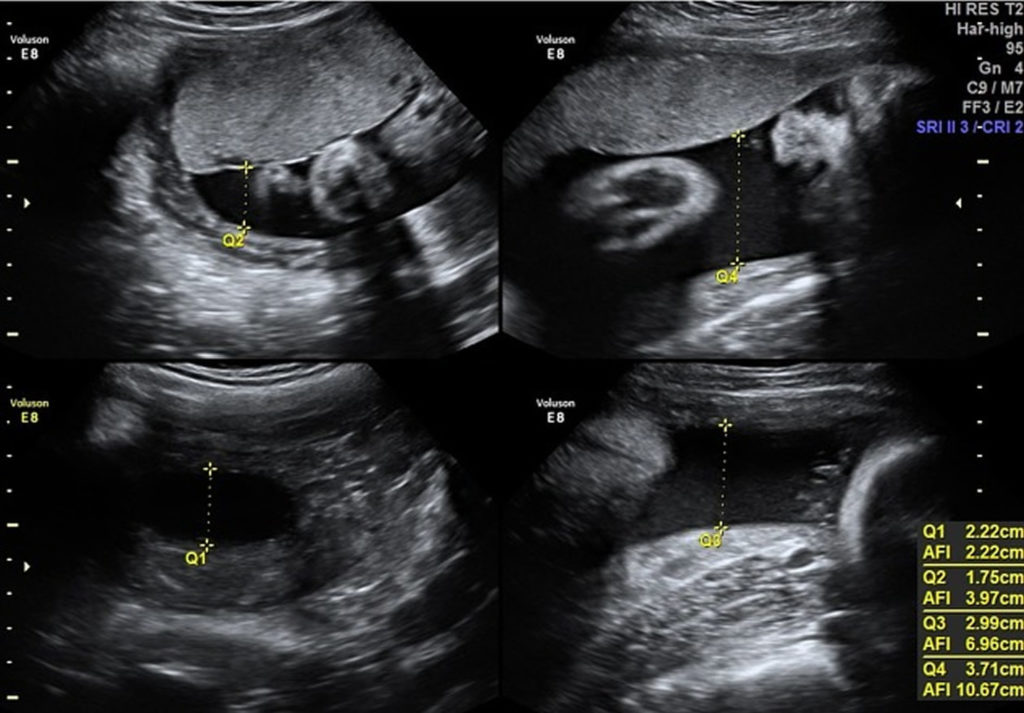

Measurement of amniotic fluid quantity How Do You Know Your Amniotic Fluid Is Low You may not know you have low amniotic fluid. Your doctor or midwife may suspect that. how do i know if i have low levels of amniotic fluid (oligohydramnios)? if your doctor is concerned that your amniotic fluids might be low, he or she may recommend an ultrasound to. while low amniotic fluid during pregnancy, or oligohydramnios,. How Do You Know Your Amniotic Fluid Is Low.